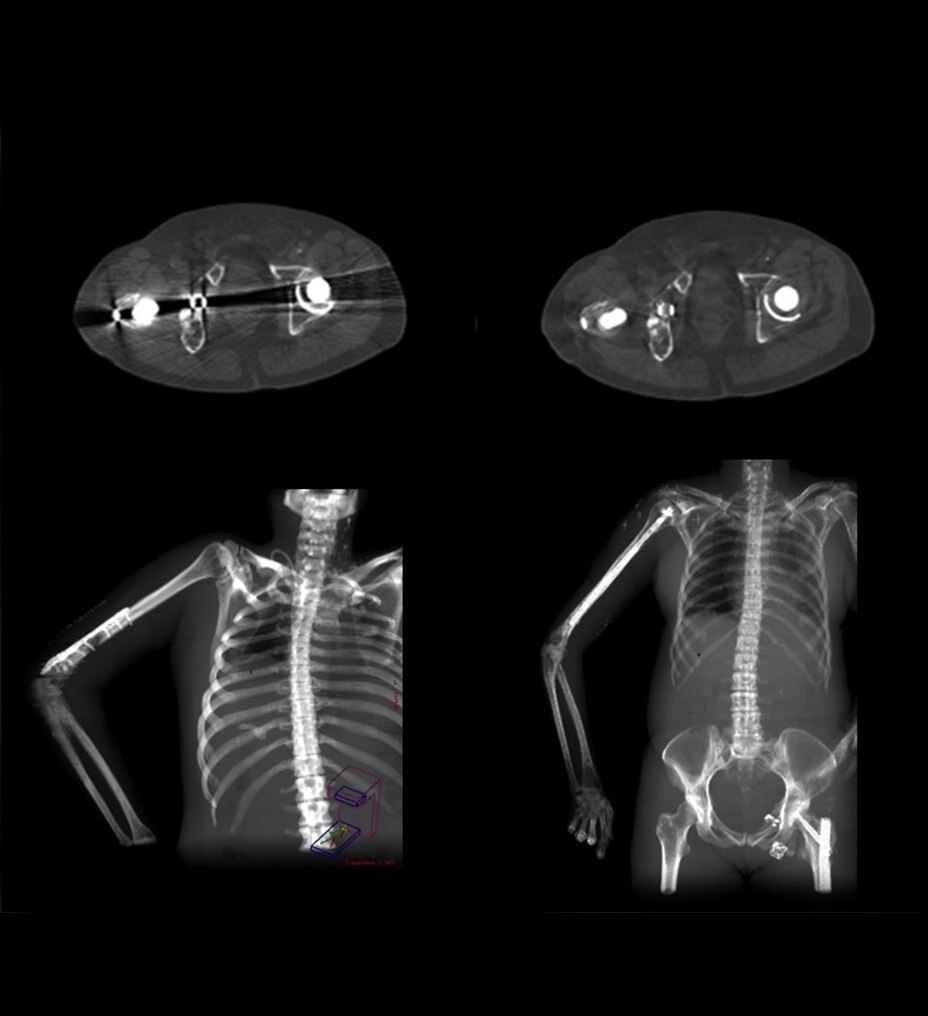

Des applications avancées pour améliorer votre flux de travail, telles que MaxFOV2, basé sur l’apprentissage profond, qui étend le DFOV à 80 cm et permet aux cliniciens de visualiser plus d’informations anatomiques, et Smart MAR 2.0 qui réduit les artefacts liés au durcissement du faisceau jusqu’à un DFOV de 80 cm.

Smart MAR 2.0

La technologie Smart MAR 2.0 est conçue pour réduire les artefacts liés aux matériaux à haute densité, tels que les implants orthopédiques, les plombages dentaires et autres éléments métalliques dans le corps. Notre technologie de correction des artefacts métalliques repose sur des données brutes, vous permettant de réduire les artefacts liés au déficit en photons et au durcissement du faisceau, révélant l’anatomie jusque-là dissimulée avec un champ d’exploration jusqu’à 80 cm.